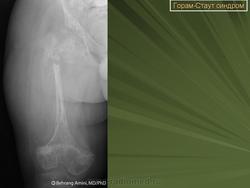

Остеолиз в области перелома кости, возникший как его осложнение. Может встречаться также при висцеромегалиях, гемангиомах кожи, капиллярных гемангиомах костного мозга, геморрагических плевритах и перитонитах.

Рентгенологическая картина

Рассасывание участка кости c образованием дефекта.

Синдром Горхэма-Стоута - Gorham-Stout - редкий синдром, при котором происходит спонтанная резорбция костной ткани. Гистологически регистрируется прогрессирующий остеолизис (osteolysis), связанный с ангиоматозом кровеносных или лимфатических сосудов.   Этиология этого заболевания не известна. Болезнь может развиться в любом возрасте, чеще  у подростков и молодых мужчин. Нет никакой родовой или расовой предрасположенности к заболеванию.